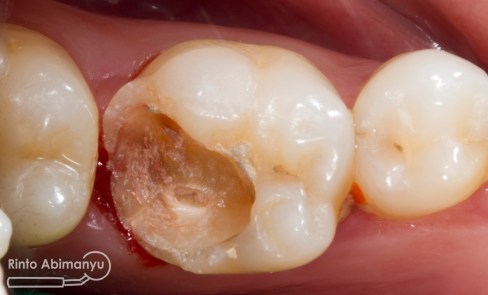

Setelah saya liat keadaan klinisnya ini yang saya lihat…

Gigi 46 terlihat kavitas masih ada karies yang sangat luas dan ada spot sudah terjadi tembus ke kamar pulpa.